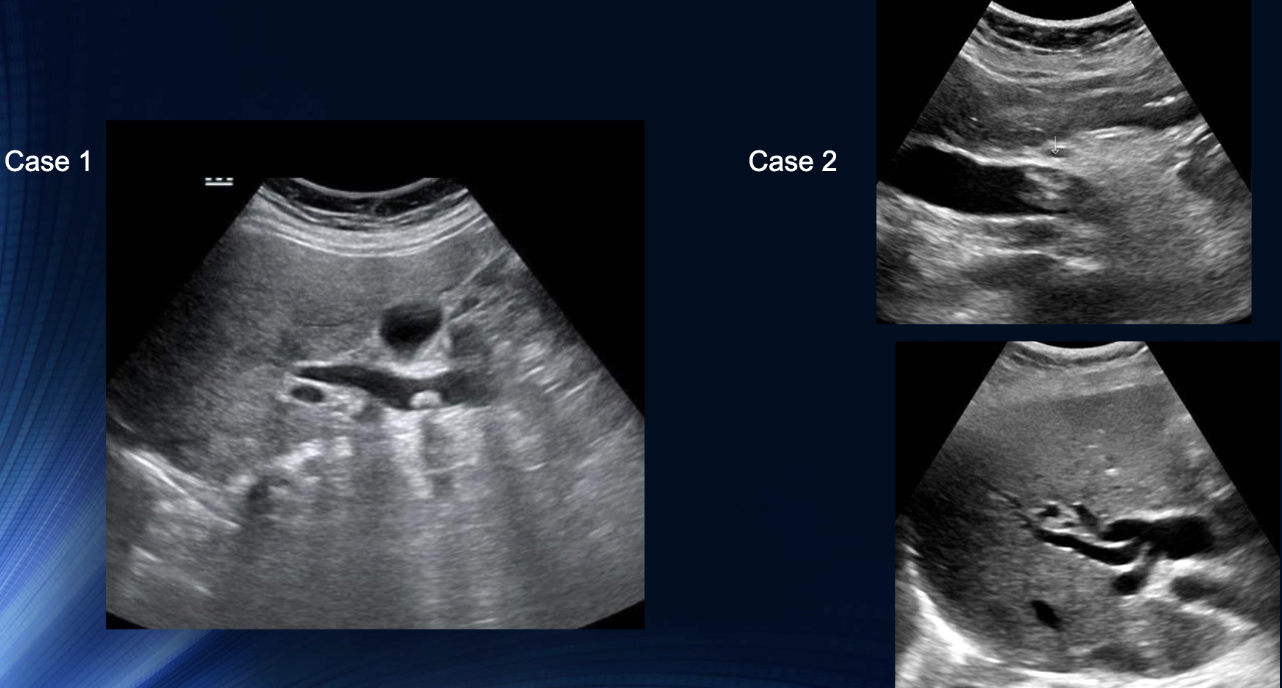

Path?

Case 1: Calculus presen with acoustic shadowing

Case 2: Common Bile Duct is Dilated + Echogenic Material Present within

Both Choledocholithiasis